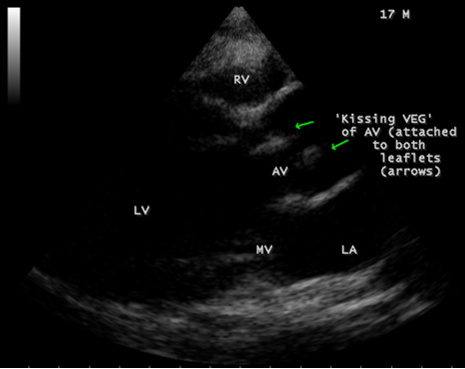

A 17-year-old female was brought to the emergency room with a history of sudden onset of breathlessness. Her pulse rate was 87 bpm and blood pressure 110/60 mmHg. She had a history of rheumatic fever during childhood, an episode of febrile illness for 10 days and taken antibiotic treatment recently. Blood chemistry revealed normal and blood cultures were negative. ECG revealed normal as shown in Figure 1 and X-ray chest revealed dilated LV (left ventricle) as in Figure 2. Physical examination revealed grade 3/6 early diastolic murmur over left mid sternal border, basal crackles over lung fields and no peripheral signs of wide pulse pressure. Transthoracic echocardiography revealed vegetations on anterior and posterior leaflets of aortic valve as in Figure 3 and Figure 4, with a “kissing-type “as in Figures 5, 6 and 8. The aortic valve was bicuspid with an attached vegetation as in Figure 9 and it was severely regurgitant as in Figure 10 and Figure 11. The left ventricle is dilated as in Figure 12 with moderate LV dysfunction as in Figure 13. The thoracic aorta was prominent as in Figure 14 with a ‘holodiastolic flow reversal’ as in Figure 15. The patient was treated with digoxin (0.25 mg, half daily), diuretics (Injection. Furosemide 20 mg IV twice daily), ACE inhibitors (tablet. Enalapril 2.5 mg twice daily) along with 2 weeks course of intravenous (IV) cefotaxime (1g) and amickacin (500mg) twice daily and advised aortic valve replacement at the earliest with lifelong penicillin prophylaxis and continuation of antibiotics for 6 weeks since the vegetations remain stable after 2 weeks of treatment, but without any embolic episodes.

Figure 5: Parasternal long axis view showing the “ kissing-type” of vegetations (arrow) on the aortic valve in a 17-year old female.

Figure 6: Parasternal long axis view showing the “ kissing-type” of vegetations (arrows) on the aortic valve in a 17-year old female- large view.

masses with atypical location. Transthoracic echocardiography detects 70% of vegetations > 6 mm and 25% of vegetation < 5>Figures 3 to 9. When endocarditis involves the aortic leaflets, the resultant acute, severe regurgitation as shown in Figures 10, 11 and 15, may often causes dilated left ventricle as in Figure 12 and a prominent aorta as in Figure 14. Secondary infection of mitral valve is a possible finding in primary aortic valve endocarditis. Large aortic valve vegetations (> 6 mm) prolapse into the left ventricular outflow tract and “kiss” the ventricular surface of the anterior mitral leaflet with the development of a vegetation [27],[28],[29]. The left ventricular outflow tract endocarditis may represent the initial site of infection with a possibility to spread by contiguity to both left-sided valves, the mitral and aortic [30], causes the “mitral-kissing vegetation” with a higher prevalence of embolic events [31].